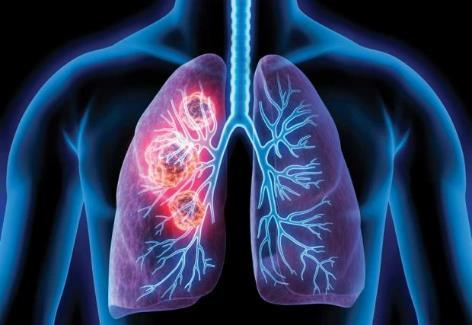

Lung Scans

Lung cancer screening is a process that's used to detect the presence of lung cancer in otherwise healthy people with a high risk of lung cancer. Lung cancer screening is recommended for older adults who are long-time smokers and who don't have any signs or symptoms of lung cancer.